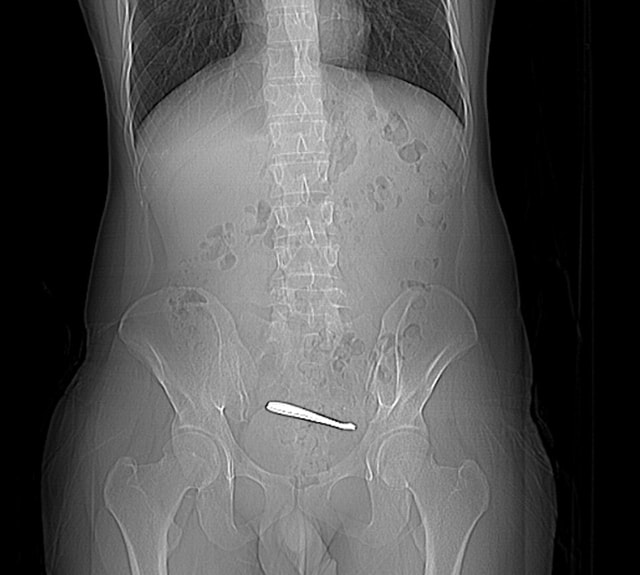

Anh Zhang, 28 tuổi, đến từ Tây An, tỉnh Thiểm Tây, Trung Quốc, gần đây đã đến bệnh viện khám chữa bệnh vì đau bụng. Kết quả chụp CT cho thấy có hai chiếc thìa trong ruột của anh.

Sau khi ông Zhang nhập viện, ông đã được chụp CT và nội soi đại tràng, kết quả cho thấy hai chiếc thìa bị mắc kẹt ở đoạn cuối hồi tràng. Niêm mạc xung quanh bị loét, tiềm ẩn nguy cơ thủng ruột. Các dị vật dài khoảng 12 cm và nằm ở đoạn ruột non hẹp, khiến việc lấy ra khá khó khăn. Sau gần một giờ phẫu thuật, các bác sĩ đã lấy thành công cả hai chiếc thìa ra nguyên vẹn bằng nội soi.